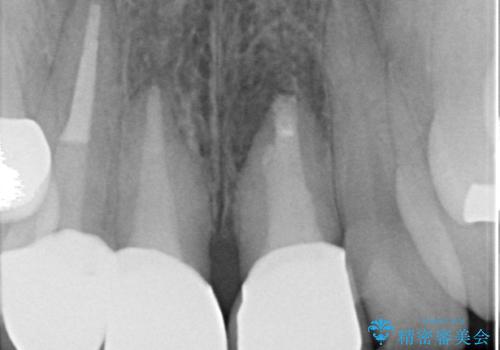

- 前歯の長さが違うのが気になるといらっしゃった方の症例です。

根尖病変を認めたため再根管治療を行った後、オールセラミッククラウン(スペシャル)にて補綴を行いました。

歯肉の腫れをより改善するため歯周外科を提案しましたが希望されませんでした。